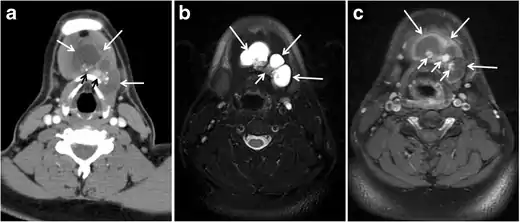

Fig. 5. A poorly differentiated invasive left thyroid mass in a 58-year-old female patient. a Sagittal greyscale neck ultrasound shows a large hypoechoic lesion with macro-calcification and micro-calcification. b Sagittal colour Doppler ultrasound shows left internal jugular vein filling defect with detected internal vascularity suggestive of tumour thrombus. c Enhanced axial and coronal CT scans of the neck show heterogeneously enhancing large lesion replacing the left thyroid lobe and extending to the isthmus and the medial aspect of the right thyroid lobe (white arrow). The mass and the conglomerate lymph nodes measure 12.5 × 7 × 5.8 cm (white arrows). d, e Axial enhanced CT scans show enlarged left cervical nodes (white arrow) and left internal jugular vein (IJV) thrombus (black arrows). Note the IJV distention and central enhancing portion in the upper cut (black arrow in e) concerning the tumour thrombus. f, g Enhanced axial CT scan of the upper chest demonstrate a mass extension into the retrosternal area, left tracheoesophageal groove, and posterior to the trachea (white arrows in f). There are multiple bilateral pulmonary nodules (white arrows in g).[1]